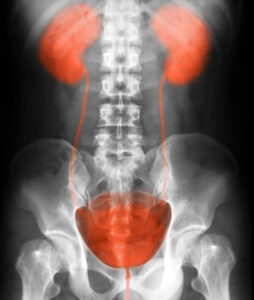

When the urinary tract is functioning properly, urine flows from the kidneys down the ureters into the bladder. Vesicoureteral reflux is diagnosed when urine flows in reverse: from the bladder back toward the kidneys. Left untreated, this retrograde flow can trigger urinary tract infections and possibly cause kidney damage. Vesicoureteral reflux affects persons of all ages, but is most commonly found among children.

- Voiding cystourethogram – When this test is performed, a very thin tube is used to inject dye into the bladder. During the test, the patient is asked to urinate while X-ray imaging is used to capture urine flow. The goal of the test is to identify if urine is flowing up the ureters toward the kidneys.